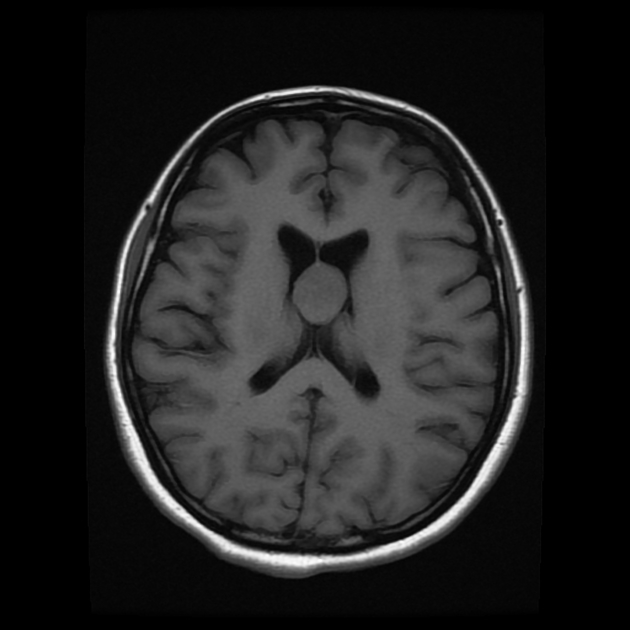

Η διάγνωση μπαίνει με την αξονική και τη μαγνητική τομογραφία. Η κολλοειδής κύστη είναι από τις λίγες περιπτώσεις όπου μπορεί να υπερτερεί η αξονική τομογραφία της μαγνητικής στην απεικόνιση.

Η υφή της είναι: στρογγυλή ενώ αποτελείται από τοίχωμα και περιεχόμενο σαν βλέννη. Στη μορφή μοιάζει με μια ρόγα από σταφύλι. Το μέγεθός της είναι 1-2 cm.

Η κολλοειδής κύστη βρίσκεται σε σημείο του εγκεφάλου που εμποδίζει τη φυσιολογική ροή του εγκεφαλονωτιαίου υγρού, με αποτέλεσμα να προκαλεί υδροκέφαλο. Αυτό μπορεί να γίνει είτε απότομα (οξύς υδροκέφαλος) με αιφνίδιο πονοκέφαλο και εμετούς, είτε σε χρόνια βάση. Η εξήγηση που δίνεται για τα επεισόδια αιφνίδιου πονοκεφάλου (δηλ. οξέος υδροκεφάλου) είναι ότι η κολλοειδής κύστη δεν είναι καθηλωμένη, με αποτέλεσμα η αλλαγή της θέσης του κεφαλιού να προκαλεί μετακίνηση της κύστης και απότομη απόφραξη της ροής του εγκεφαλονωτιαίου υγρού. Η θεωρία της ευκίνητης κύστης, που «μετακινείται», δεν επιβεβαιώνεται γενικά στις χειρουργικές επεμβάσεις αφαίρεσης της κύστης.